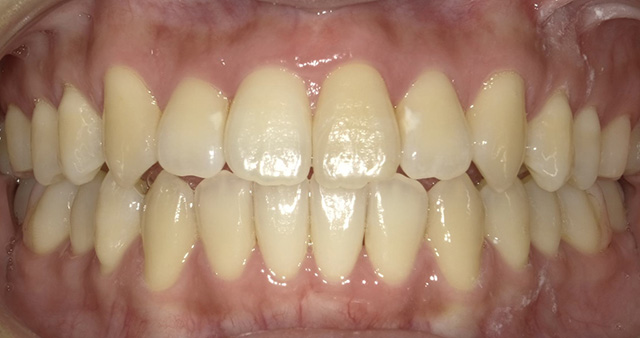

マウスピース型の矯正器具を装着して歯を動かす治療です。マウスピースは透明の医療用のプラスチック製で、目立たず、周囲に気づかれずに治療が受けられるという特徴があります。取り外しが可能で、いつも通りに食事や歯みがきをすることができます。